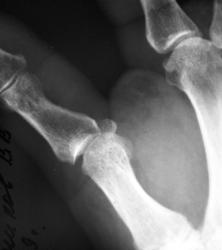

Катенёв Валенти... Дата публикации 01.05.2009, 12:06 Пациент направлен хирургом с диагнозом "перелом". Произвели рентгенографи. Вопрос заключается в том, что данное состояние должно быть обозначено, как "вывих" или "переломовывих"? Пт, 01/05/2009 - 12:46 #1 flagman Не на сайте Был на сайте: 11 лет 5 месяцев назад Зарегистрирован: 05.06.2008 - 20:08 Публикации: 83 а если перелом, вывих. Пт, 01/05/2009 - 12:48 #2 Катенёв Валенти... Не на сайте Был на сайте: 7 лет 4 недели назад Зарегистрирован: 22.03.2008 - 22:15 Публикации: 54876 Спасибо за высказанное мнение. Пт, 01/05/2009 - 13:58 #3 Ермолаев Не на сайте Был на сайте: 8 лет 10 месяцев назад Зарегистрирован: 07.02.2009 - 16:33 Публикации: 670 Валентин Львович! Мое мнение, что имеется вывих и перелом. Два разных костно-травматических изменения с точки зрения патологической анатомии. dok Пт, 01/05/2009 - 14:00 #4 Катенёв Валенти... Не на сайте Был на сайте: 7 лет 4 недели назад Зарегистрирован: 22.03.2008 - 22:15 Публикации: 54876 Спасибо за высказанное мнение. Пт, 01/05/2009 - 14:47 #5 Петрович Не на сайте Был на сайте: 7 лет 2 месяцев назад Зарегистрирован: 22.03.2009 - 01:13 Публикации: 3908 Господа и товарищи! Перелом чего? Неоднозначно всё Сб, 02/05/2009 - 14:39 #6 mihail72 Не на сайте Был на сайте: 11 лет 1 месяц назад Зарегистрирован: 20.06.2008 - 17:49 Публикации: 4 Вывих и мелкооскольчатый перелом основания проксимальной фаланги Сб, 02/05/2009 - 15:53 #7 Петрович Не на сайте Был на сайте: 7 лет 2 месяцев назад Зарегистрирован: 22.03.2009 - 01:13 Публикации: 3908 Показал бы кто пальчиком а) мелкие осколки б) откуда откололись. Кортикальный слой кости и его фрагменты должны быть видны чётко! Неоднозначно всё

Валентин Львович! Мое мнение, что имеется вывих и перелом. Два разных костно-травматических изменения с точки зрения патологической анатомии.

Вывих и мелкооскольчатый перелом основания проксимальной фаланги